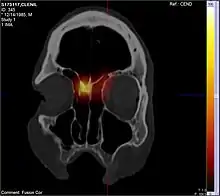

CT scan

CT scan can show the full extent of the polyp, which may not be fully appreciated with physical examination alone. Imaging is also required for planning surgical treatment.[7] On a CT scan, a nasal polyp generally has an attenuation of 10–18 Hounsfield units, which is similar to that of mucus. Nasal polyps may have calcification.[14]